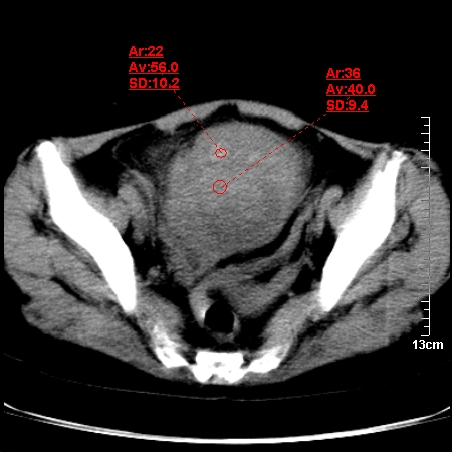

术前的疏忽,手术前诊断阑尾炎,但是没有常规做b超,导致术后1周检查发现 1。实性包块?2。腹腔术后脓肿?

病史:病人一周前诊断阑尾炎,未做b超,手术发现阑尾化脓,(没有留意有无包块),术后1周病人发热,血象:1.6万,做b超发现,随ct检查,上传图片

巨大囊实性包块,边界大部尚清楚,不太像脓肿的表现。应该做个增强检查除外盆腔肿瘤。

脓肿可能性大. 因回盲部区域化脓性兰尾切除残端感染改变征像与实性肿块关系密切.肿块上界至右下腹,下界至盆腔膀胱上缘, 如果是实性肿块在兰尾术中可能就会发现. 所以术后一周病人高烧, 白细胞增高,临床表现支持脓肿.

盆腔一边界大部份清晰囊实性肿块,其周腹脂未见确切异常,其一端与右侧附件相连。考虑右侧附件肿瘤。

实质性囊腺瘤可能